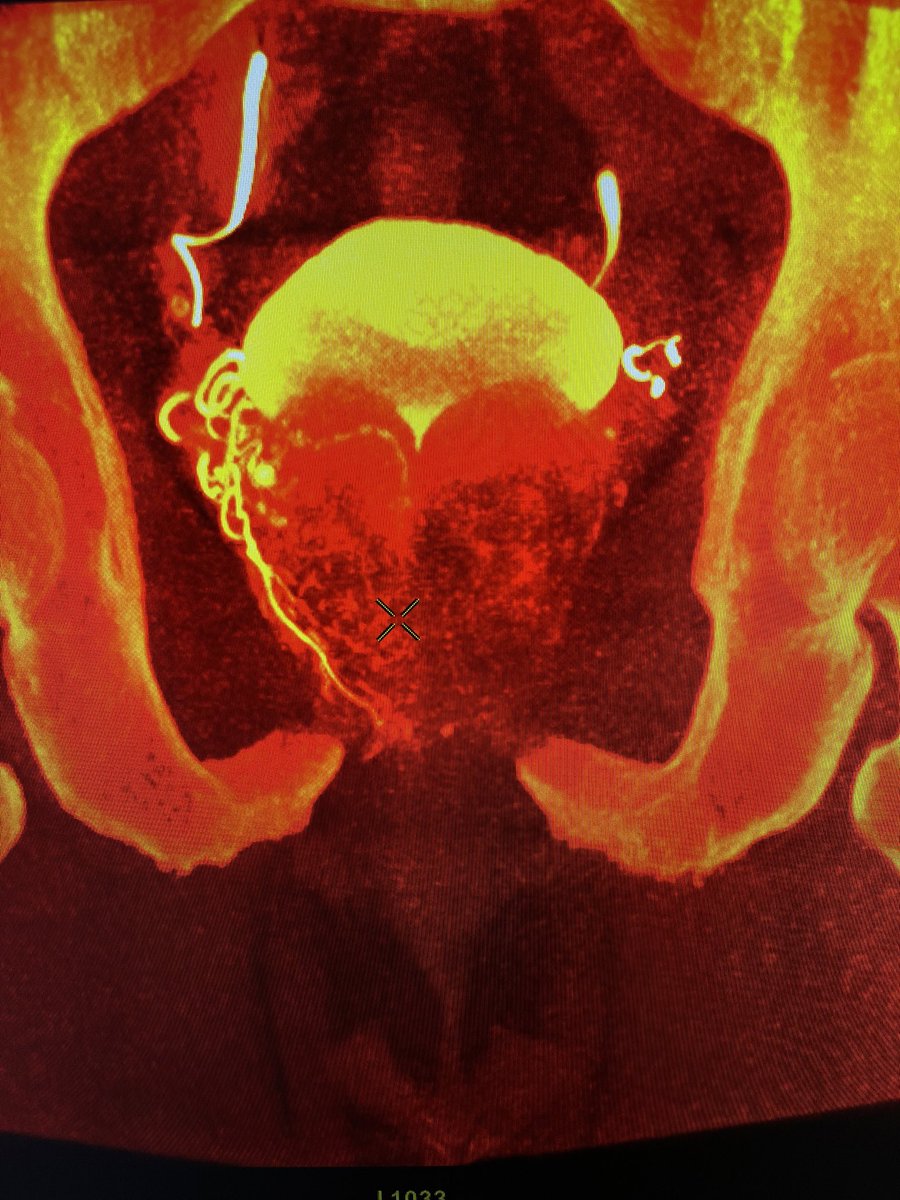

3 vessels supplying the left side of the prostate. Not uncommonly found on redo’s. This patient is 5 years out from his first PAE. What size particles would you use? Coils? Come join us at STREAM in DC. STREAMmeeting ECCO Medical thestreammeeting.com/events/stream-…